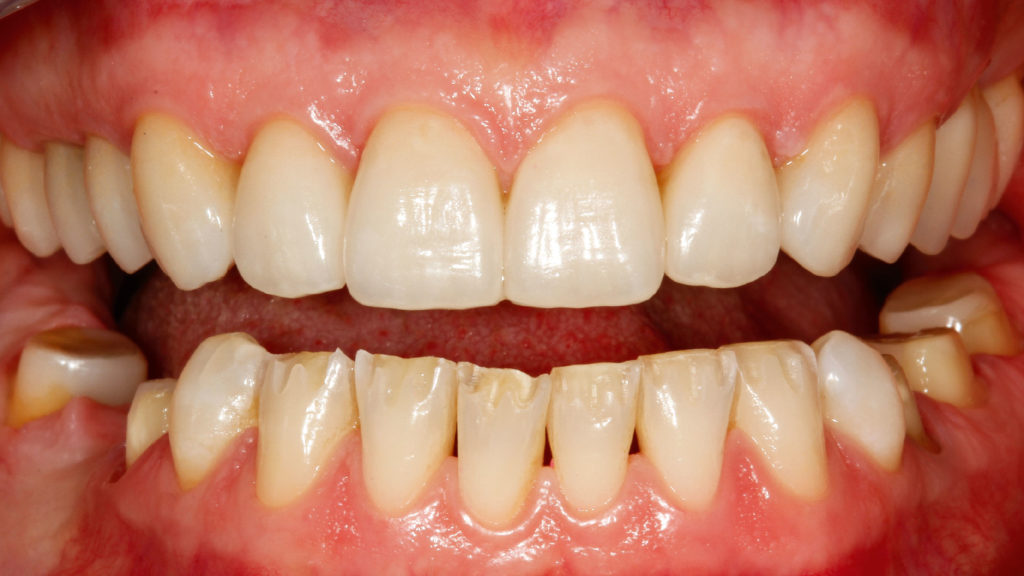

Im Labor konnten die vollkeramischen Restaurationen in der Presstechnik hergestellt werden (Abb. 8 bis 11). Die exakte Bisshöhe wurde zuvor im Mund evaluiert. Herstellung und Eingliederung der Veneers gestalteten sich dank des Wellenschliffs deutlich einfacher als mit anderen Veneer-Präparationsarten, da die Restaurationen am Zahn eine definierte Position hatten. Die adhäsive Eingliederung folgte den bekannten Abläufen. Die keramischen Restaurationen wurden geätzt beziehungsweise für das Verkleben konditioniert (Abb. 12). Nach dem Reinigen der Zähne wurden die Oberflächen mit Phosphorsäuregel vorbereitet, abgespült und getrocknet, mit Primer vorbehandelt, und es wurde Haftvermittler beziehungsweise Bonder aufgetragen (Abb. 13 bis 17). Nach dem Applizieren des Befestigungsmaterials konnten die Restaurationen eingegliedert und Materialüberschüsse entfernt werden (Abb. 18 und 19). Nach der Lichthärtung wurden die Ränder geglättet und die approximalen Kontakte angepasst sowie final poliert (Abb. 20 bis 24). Dabei zeigte sich ein weiterer Vorteil des Pfullinger Wellenschliffs. Der Übergang zwischen Zahn und Keramik ist dank des „diffusen“, bewusst unregelmäßig angelegten Präparationsdesigns optisch kaum wahrzunehmen. Eine Kontrolle der funktionellen Gegebenheiten bildete den Abschluss der prothetischen Therapie. Die in der Initialphase stabilisierte neue vertikale Bisshöhe konnte 1:1 mit den keramischen Restaurationen übernommen werden (Abb. 25).

Grundsätzlich ist es bei einer solchen Therapie unverzichtbar, während der prothetischen Phase die neue Bisshöhe zu erhalten. Daher wurde wie im ersten dargestellten Fall zunächst der Oberkiefer präpariert, mit Provisorien versorgt und im Unterkiefer die Schiene wieder eingegliedert. Nach der therapeutischen Phase wurden im Labor die vollkeramischen Restaurationen hergestellt. Während im vorangegangenen Fall indirekte temporäre Kompositrestaurationen („Deckel“) für die Unterkiefer-Frontzähne im Labor erstellt worden waren, kam in diesem Fall – aufgrund des vergleichsweise geringen Platzangebots – die direkte Methode zur Anwendung. Nach dem Einsetzen der vollkeramischen Restaurationen im Oberkiefer diente ein im Labor auf der Basis eines Wax-ups hergestellter Silikonschlüssel (transparentes Formteil) dem Herstellen temporärer Chairside-Restaurationen aus lichthärtendem Komposit. Der Patient testete in den folgenden Wochen die Situation und die neue Bisslage. Danach erfolgte die Präparation der Zähne im Unterkiefer. Die Zähne 46, 47, 35, 36 (Implantat), 37, 38 wurden für die Aufnahme von Kronen und 44/34 sowie 45 für Teilkronen (mit vestibulärem Wellenschliff) vorbereitet und die Frontzähne im Sinne eines optimalen Substanzerhalts nach dem „Pfullinger Wellenschliff“ präpariert (Abb. 27). Zahn 41 hatte bereits eine Krone, weshalb dort die Präparation nur leicht angepasst worden ist. Bei diesem Fall wurde ein reduzierter Wellenschliff vorgenommen. Das Herstellen der keramischen Restaurationen sowie die adhäsive Eingliederung folgten dem im Fall 1 beschriebenen Vorgehen (Abb. 28 bis 34). Erneut spielte der Wellenschliff seine Vorteile aus: vereinfachtes Handling in Praxis und Labor, geringe Invasivität sowie aufgrund des unregelmäßig verlaufenden Präparationsrands diffuser, augenscheinlich nicht sichtbarer Übergang zwischen Zahn und Keramik.